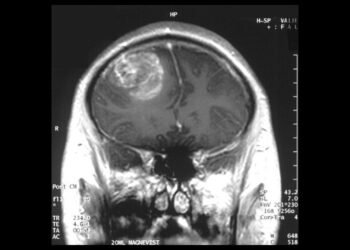

Terapia qelizore CAR-T, rezultate pozitive për të luftuar kancerin

Ekspertët kanë testuar një metodë të re ndaj terapisë qelizore CAR-T, e cila është një mënyrë për të marrë qelizat ...